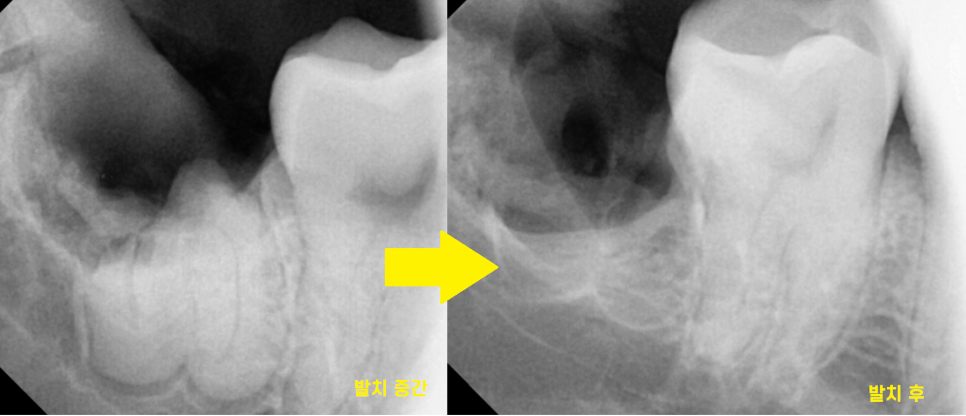

23.07.10

신경과 근접해 있기 때문에

최대한 조심스럽게

치아를 조각내 문제없이

깨끗하게 뽑아드렸습니다.

깔끔하게 뽑아드렸습니다.